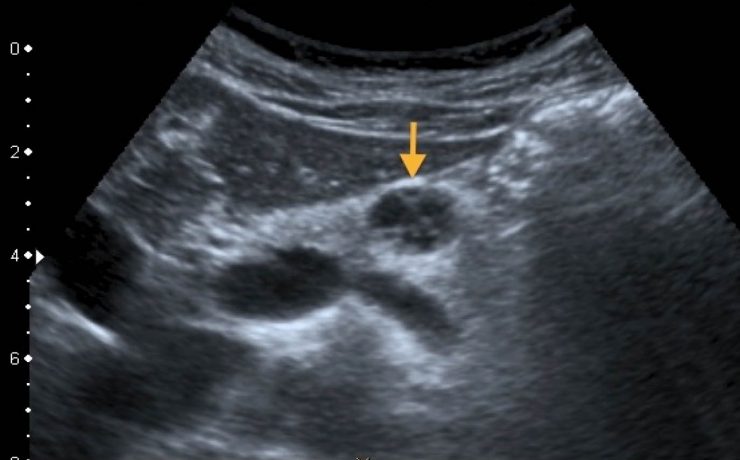

Nódulo de tiroides

La glándula tiroides es con frecuencia afectada por diferentes patologías de tipo funcional y orgánico, que conllevan a cambios funcionales y estructurales de este órgano. Cuando estos cambios son estudiados por medios radiográficos, arrojan una serie de imágenes características que contribuyen con una de las funciones médicos sociales más importantes,